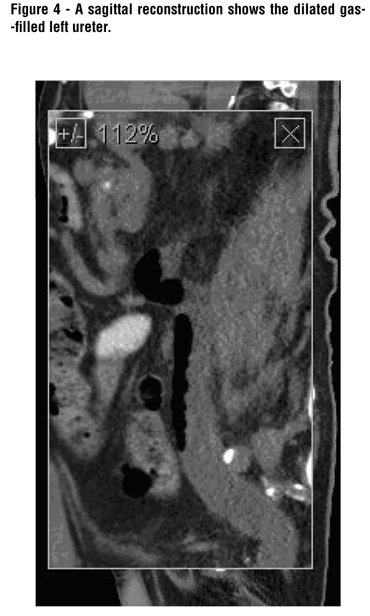

A three-phase contrast-enhanced CT (with intravenous contrast medium reduced to 60 mL, because of elevated creatinine) was performed with both coronal and sagittal reconstructions. An axial slice showed a hugely dilated left ureter with an air fluid level (Figure-1). A coronal reconstruction ( the area of interest enlarged to156%) demonstrates gas in the fistula to the thickwalled segment of the sigmoid colon as well as at the level of the UPJ (Figure-2). Diverticula are shown in the third portion of the sigmoid colon. An aneurysm of the infra-renal segment of the aorta was noted. Another coronal reconstruction (206% enlargement of area of interest) at a slightly more posterior level shows the entire left ureter dilated by gas (Figure-3). A sagittal reconstruction shows the dilated gas-filled left ureter (Figure-4).